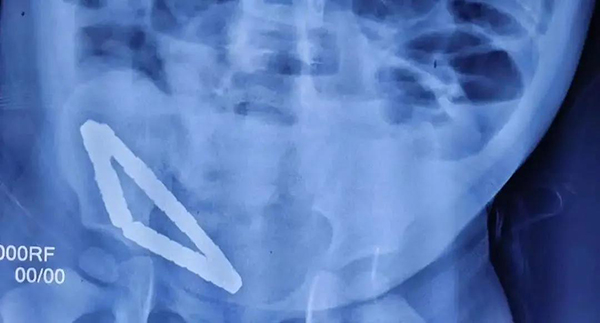

X片顯示磁力珠在孩子體內(nèi)連成一串   呂品攝影

8月4日,徐州市兒童醫(yī)院接診一名1歲9個(gè)月的男童彬彬(化名),據(jù)患兒家長(zhǎng)口述,孩子連續(xù)幾天高燒不退,嘔吐且無(wú)法進(jìn)食,一直哭鬧不止。患兒在當(dāng)?shù)蒯t(yī)院檢查拍X片查出腹腔內(nèi)有異物,消化道已穿孔,因當(dāng)?shù)蒯t(yī)院無(wú)法處理轉(zhuǎn)院至徐州市兒童醫(yī)院。

“接診時(shí),患兒已出現(xiàn)精神萎靡,腹脹如鼓,必須立即實(shí)施手術(shù)。”曹慧主任說,“手術(shù)中發(fā)現(xiàn),患兒體內(nèi)居然有31顆磁力珠,這些磁力珠在患兒腸道內(nèi)互相吸附,連成一串。因?yàn)檫@種磁力珠吸力特別大,將患兒小腸緊緊'夾'住,造成患兒三處腸壞死和腸穿孔。因?yàn)榇帕χ榈拇判院軓?qiáng),如果太用力分離磁力珠會(huì)導(dǎo)致腸壁破損更嚴(yán)重,所以整個(gè)手術(shù)只能小心翼翼進(jìn)行……最終我們將患兒體內(nèi)的31顆磁力珠全部取出,并截掉壞死小腸20cm左右,才算保住了孩子的性命。目前孩子已經(jīng)度過危險(xiǎn)期,康復(fù)狀態(tài)良好。”